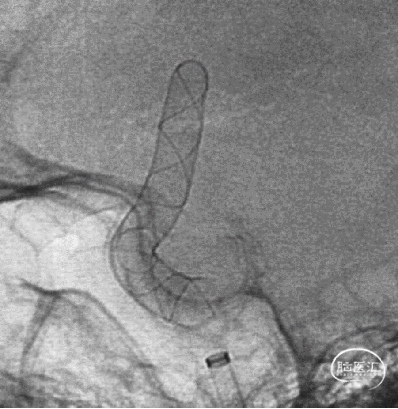

TB Plus 4/35

3、释放TB Plus过程中,头端铆钉效果满意,释放过程顺滑。

4、通过微导丝按摩,可以使TB Plus贴壁效果更加。

6、Tubridge Plus材料改进后通体显影,可以更好观察支架的贴壁性及术中打开情况,提高释放安全性。